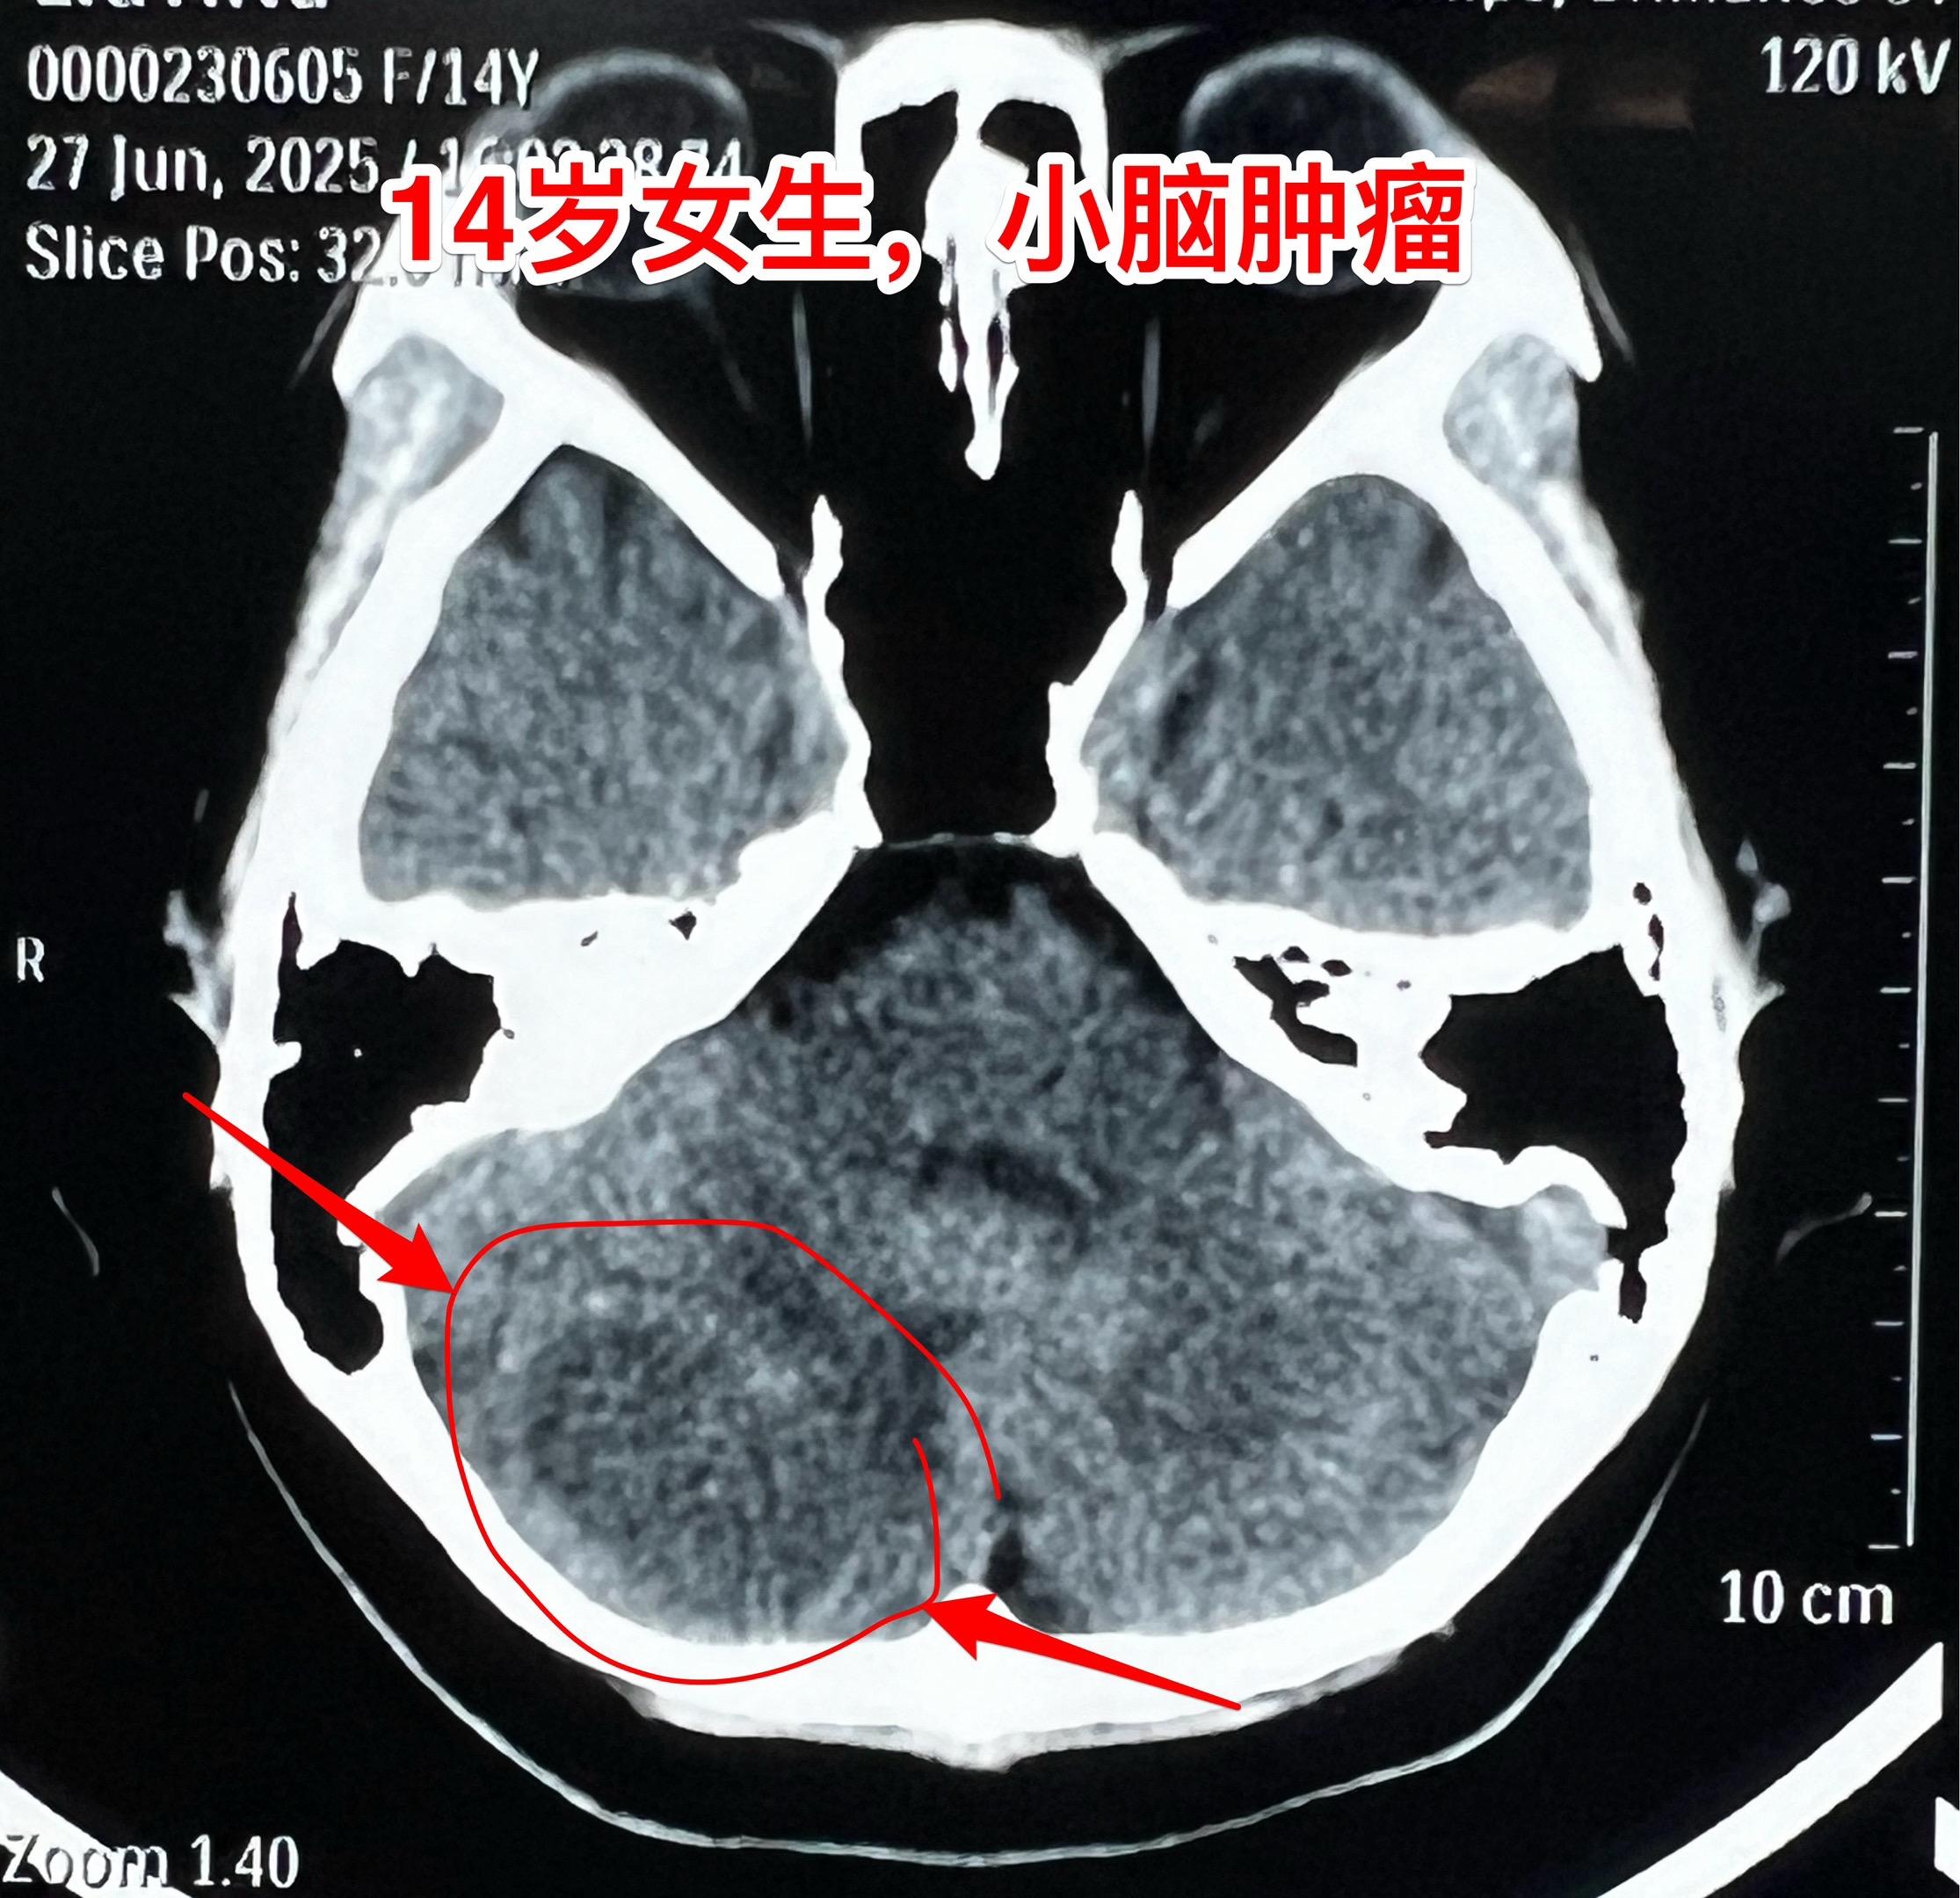

小孩子脑肿瘤中最常见的是小脑肿瘤。与大人相比,小孩子一般是不容易患上肿瘤性疾病的。然而,小孩子也会患上肿瘤性疾病,其中包括脑部肿瘤、白血病、骨肿瘤等等。 小孩子的脑肿瘤中最常见的小脑肿瘤,小脑肿瘤经常导致病人呕吐。所以,小孩子在没有感冒症状的前提下出现反复呕吐症状,要想到脑部是不是出了问题? 这个14岁沧州女生平常身体很健康,近5天感觉头晕、恶心、呕吐,在当地医院就医,行脑部磁共振、CT检查发现了小脑肿瘤。用甘露醇降颅压后她的症状明显减轻了。6月27日下午到我科来住院,6月2